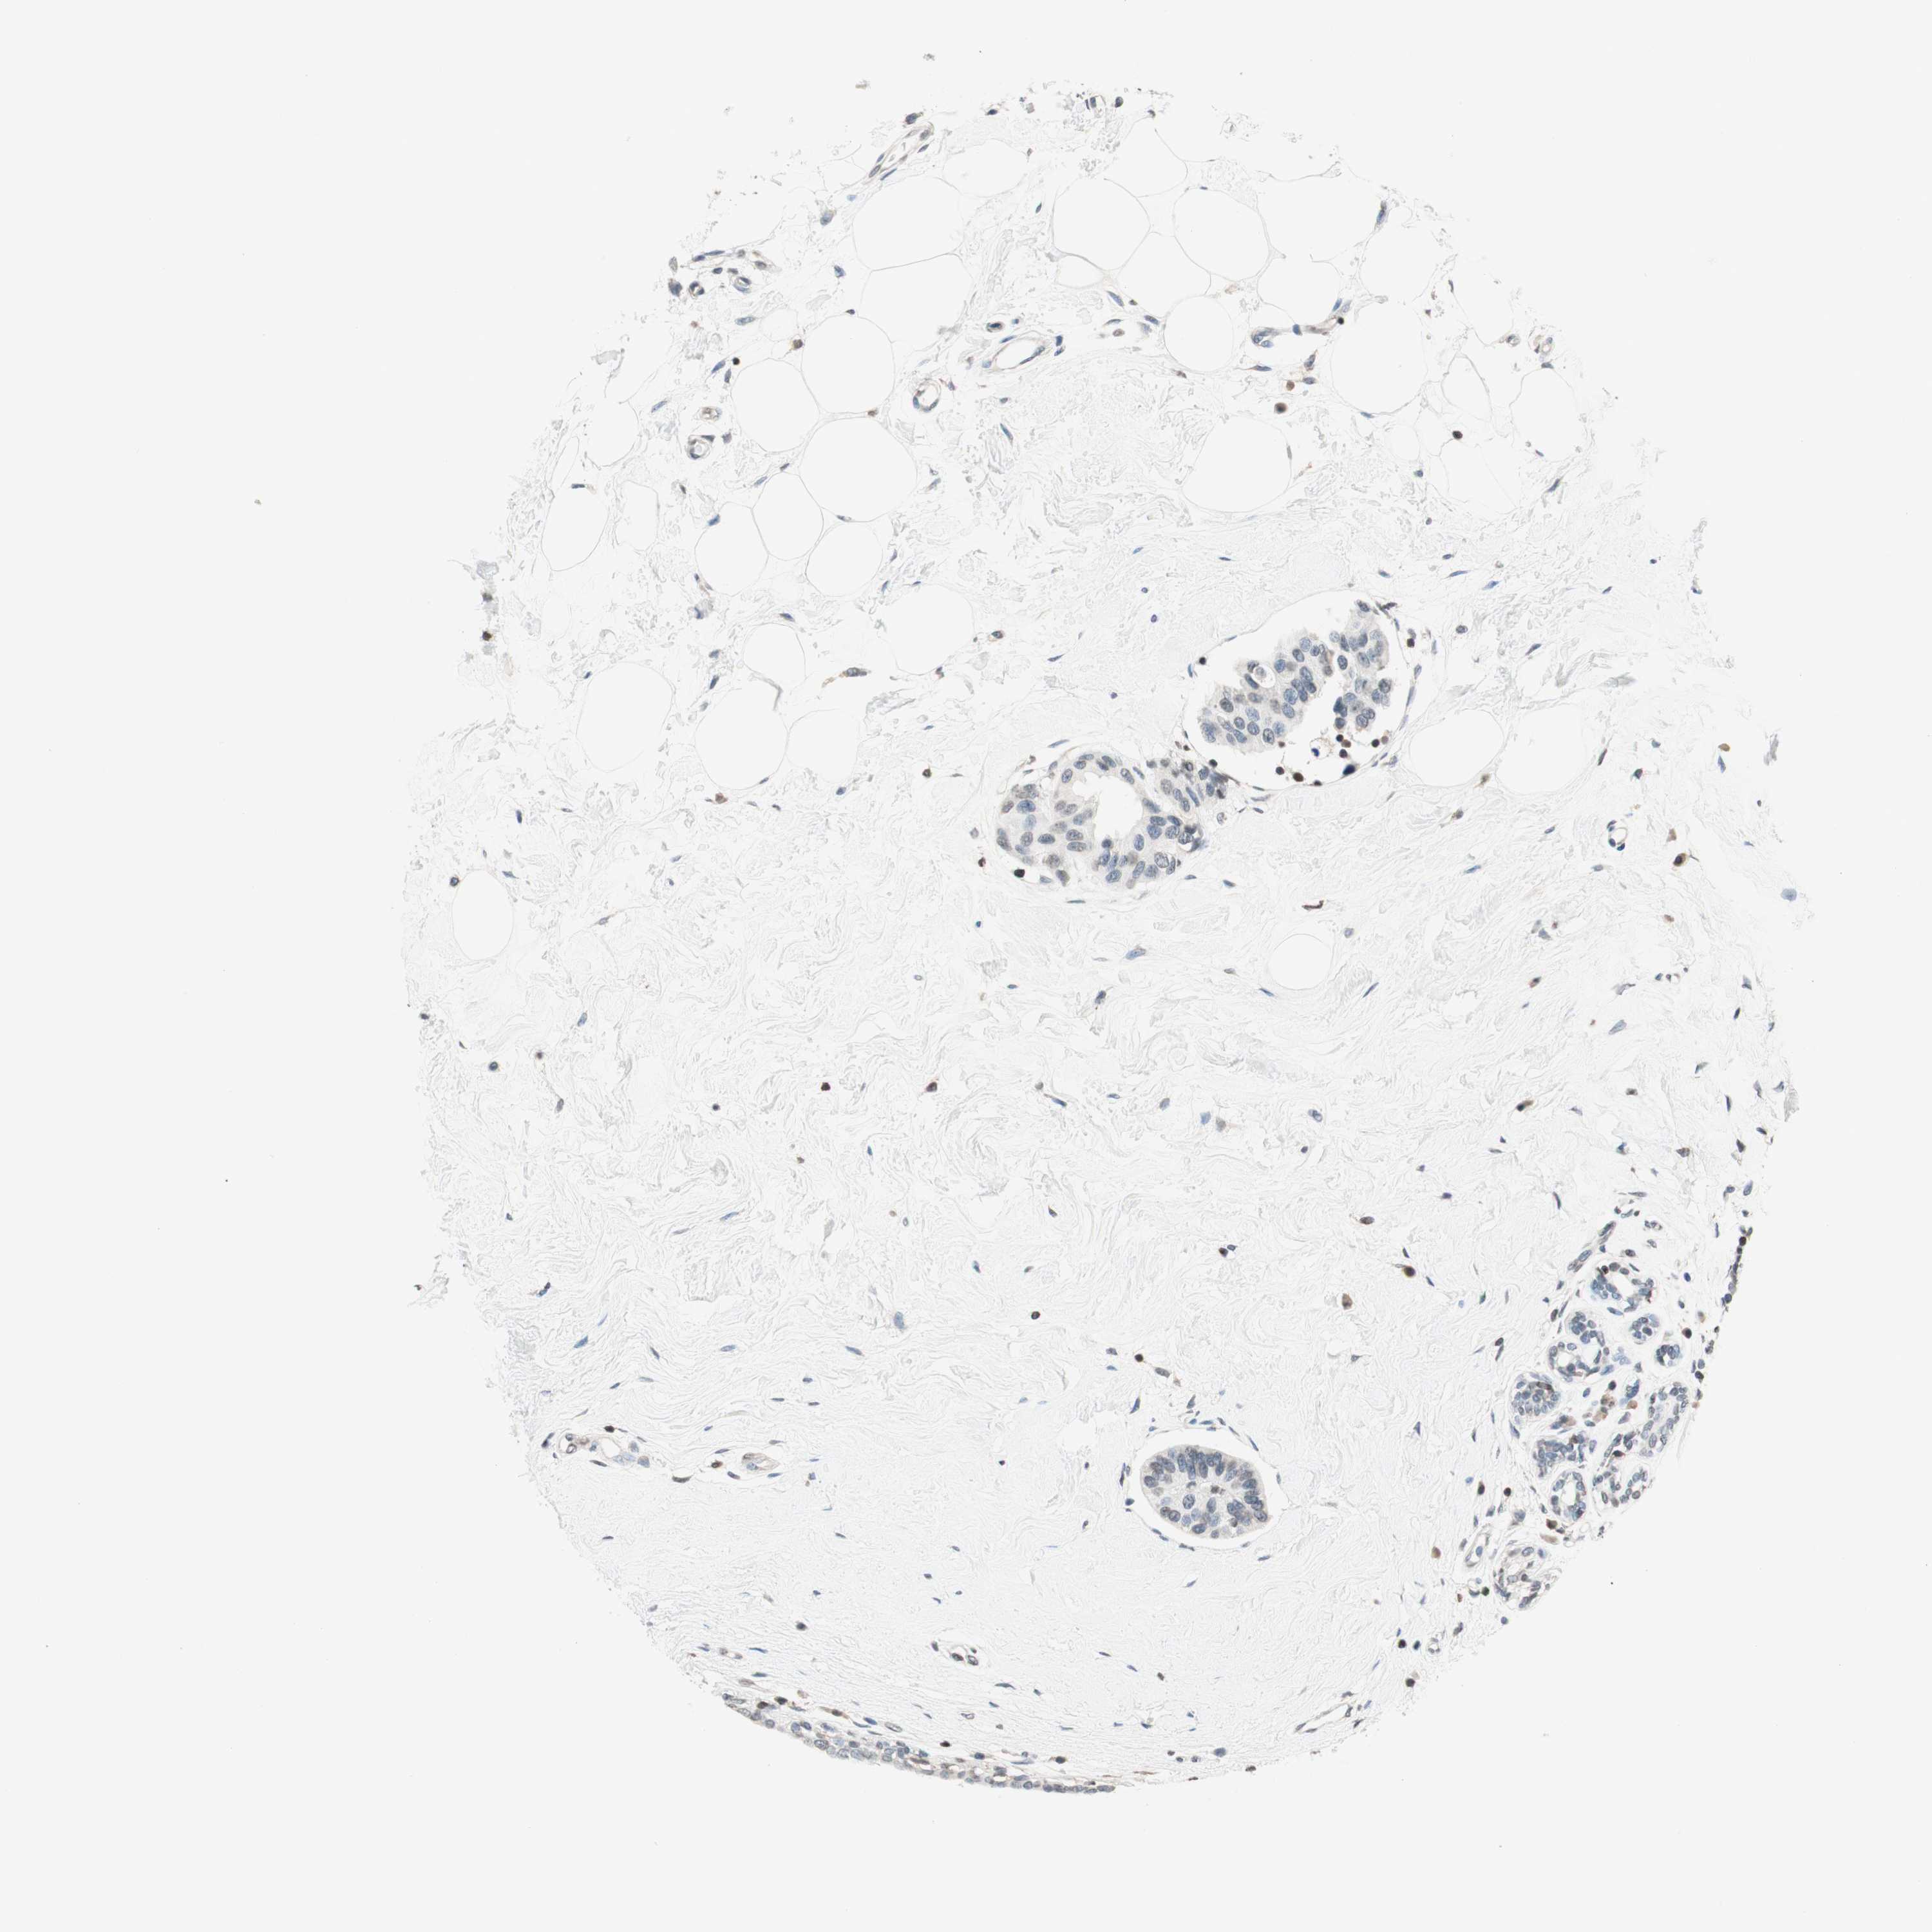

BRCA TCGA BRCA VALIDATION PROTEIN EXPRESSION

ANTIBODIES

AND

VALIDATION